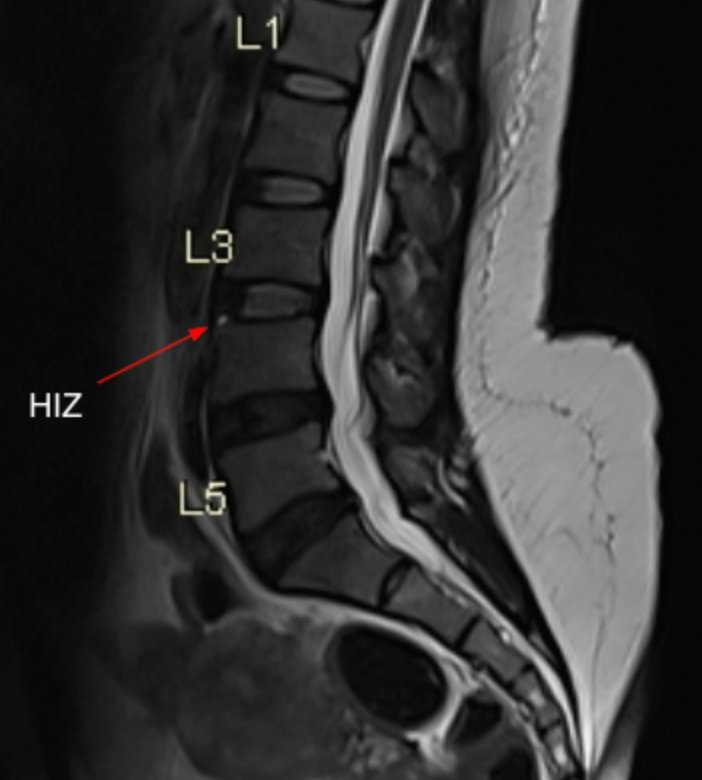

Image Type Lumbar Spine X-Ray CT Scan MRI Scan Anteroposterior (AP) Canal Diameter Cauda Equina Nerve Root Area Conus Medullaris Level Cross-Sectional Area (CSA) of Spinal Canal Disc-Height Index (DHI) Disc Herniation Size Disc Herniation Types Dural Sac CSA Epidural Fat Thickness Filum Terminale Thickness Foraminal Height and Width High-intensity Zone (HIZ) Lateral Recess Width/Depth Modic Endplate Changes (Type I, II, III) Modic (Marrow Signal) Changes Pfirrmann Classification (I-V) Vertebral Bone Quality (VBQ) Score Vertebral Endplate Defects